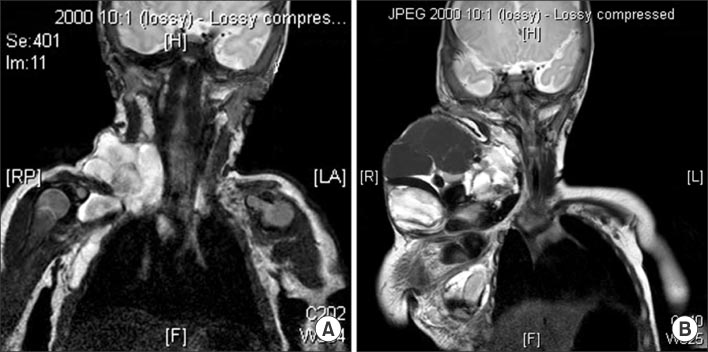

Fig. 5

(A) Sagittal T2-weighted MRI shows cervical lymphangioma which are infiltrating tongue base (patient No. 11). (B) Decreased lymphatic malformation after surgery.